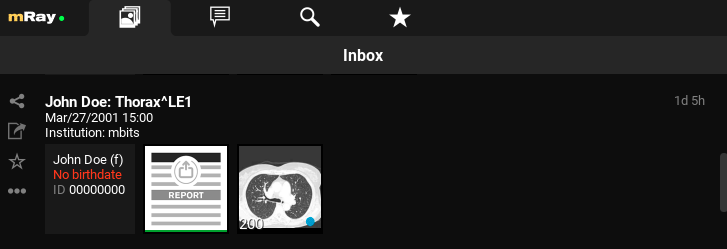

9.1. Inbox

The (Inbox) will be opened after logging in. With this you can browse and select the wanted DICOM files, which are enabled for you through the server. Thus you can see all files on the mRay server on which you have access rights.

Shows information or rather missing information and meta data from a patient.

Shows an overview of the contained series in a study. By clicking a study you will get to the series selection (see Series selection). The green marker under any thumbnail indicates that the image data is stored locally and offline available.

The time will appear as soon as the data arrived in the mRay (by sending from a PACS and searching in the mRay database). mRay can be configured to automatically delete data after 'X' hours (default: after 8 hours).